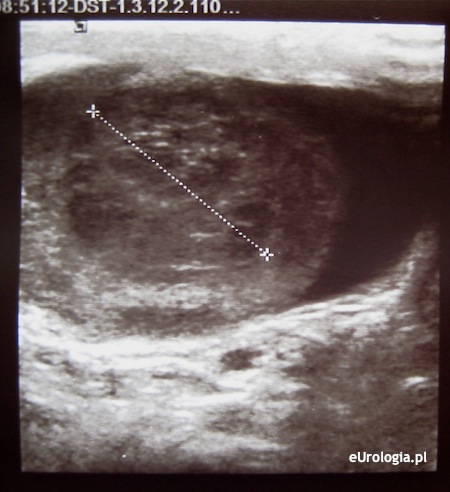

Badanie USG jąder charakteryzuje blisko 95% skutecznością w wykrywaniu guzów jądra. W badaniu ultrasonograficznym guzy jądra widoczne są jako hipoechogeniczne kuliste obszary o jednorodnej echostrukturze z dobrze widocznymi granicami. Czasami w obrębie guza mogą być widoczne przestrzenie płynowe. Guzy jądra mogą być jednoogniskowe lub wieloogniskowe. W opcji kolorowego Dopplera w obrębie guza widoczny jest wzmożony przepływ w obrębie patologicznej zmiany.

Fot. Guz dolnego bieguna prawego jądra - obraz USG